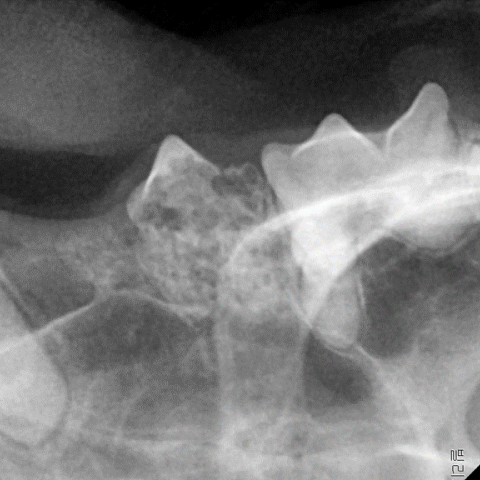

АэОчРЬ ФЁОЦШэМіМККДКЏ

(Feline Odontoclastic Resorption Lesion)

АэОчРЬШэМіМККДКЏРК ФЁОЦРЧ ЦФФЁ ММЦї(odontoclasts)РЧ КёСЄЛѓРћРЮ ШАЕПРИЗЮ РЮЧи РќУМ ФЁОЦ ЧЅИщПЁ МеЛѓРЬ ГЊХИГЊДТ СњШЏРдДЯДй. ФЁОЦ Аб КЮКаРЛ АЈНб ПЁГЊИсУўРЬ МеЛѓЕЧИщ ФЁОЦ ОШТЪРЧ ФЁСжАќРЬ ГыУтЕЧИщМ УтЧї, ПАСѕ, ХыСѕРЛ РЯРИХААд ЕЫДЯДй.

ФЁОЦШэМіМККДКЏРЬ Л§Бф ФЁОЦДТ ЦФФЁ ММЦї ШАЕПРИЗЮ РЮЧи ФЁОЦАЁ ГьБт ЖЇЙЎПЁ РАОШРћРИЗЮ ХЉБтАЁ РлАХГЊ ФЁОЦРЧ РЯКЮАЁ АсМе ЕЧОю РжДТ АцПьАЁ ИЙНРДЯДй. РАОШРћРИЗЮ КДКЏРЬ РЧНЩЕЩ АцПь ФЁАњЙцЛчМБ АЫЛчЗЮ ШЎРЮЧЯПЉ СјДмРЛ ГЛИЎАд ЕЫДЯДй.

ОрЙА ФЁЗсДТ БйКЛРћРЮ ФЁЗсАЁ ЕЩ Мі ОјОю ЙЎСІАЁ ЕЧДТ ФЁОЦИІ ЙпФЁЧЯДТ АЭРЬ АЁРх ШЎНЧЧб ФЁЗсЙ§РдДЯДй. ДйИИ ФЁОЦШэМіМККДКЏРЬ Л§Бф ФЁОЦРЧ АцПь ФЁОЦ ЛбИЎАЁ РЬЙЬ ФЁСЖАёАњ РЏЧеЕЧОю РжРЛ Мі РжОю ФЁАњЙцЛчМБ АЫЛч ШФ ЙпФЁ ЙќРЇИІ АсСЄЧиОп ЧеДЯДй.